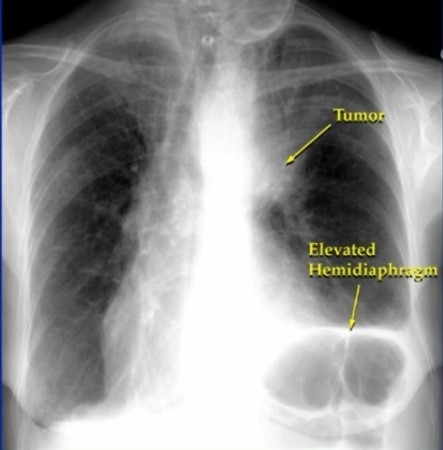

폐암에 걸리면 흉부에 고통이 느껴집니다. 폐의 가장자리에 생긴 폐암이 흉막과 흉벽을 침범하여 고통이 생기는 것으로 가슴이 답답하면서 꽉 막힌 느낌이 지속되며 날카롭게 찌르는 듯한 느낌과 압력 하는 느낌 등 여러 가지 고통이 나타나요.

폐암 종양이 자라면서 상반신의 혈액을 모으는 상대정맥을 압박할 수 있습니다. 이것이 바로 '상대정맥 증후군'이라고 합니다. 상대정맥 증후군이란 상대정맥 주위에 종양이 생겨 압박이 생기는 증상입니다. 이것은 혈액의 순환 장애를 유발하며 머리와 팔이 붓거나 가슴 정맥 돌출, 호흡곤란 등의 증상으로 이어집니다. 또한 가슴 부위 피부가 푸르스름한 색을 띠게 됩니다.